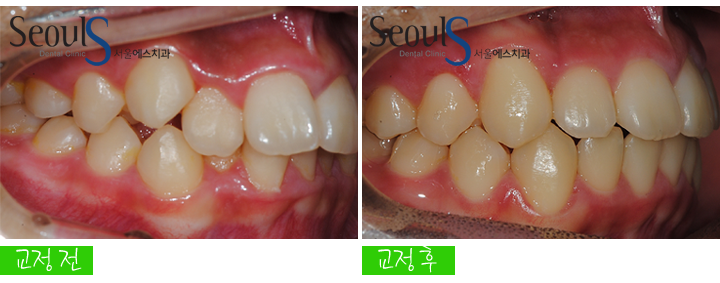

측면 모습입니다

측면 모습입니다

치열이 가지런하지 못합니다

교정 후 측면 모습입니다

교정 전후 측면 모습입니다

반대편 측면도 가지런하게 교정된 모습입니다